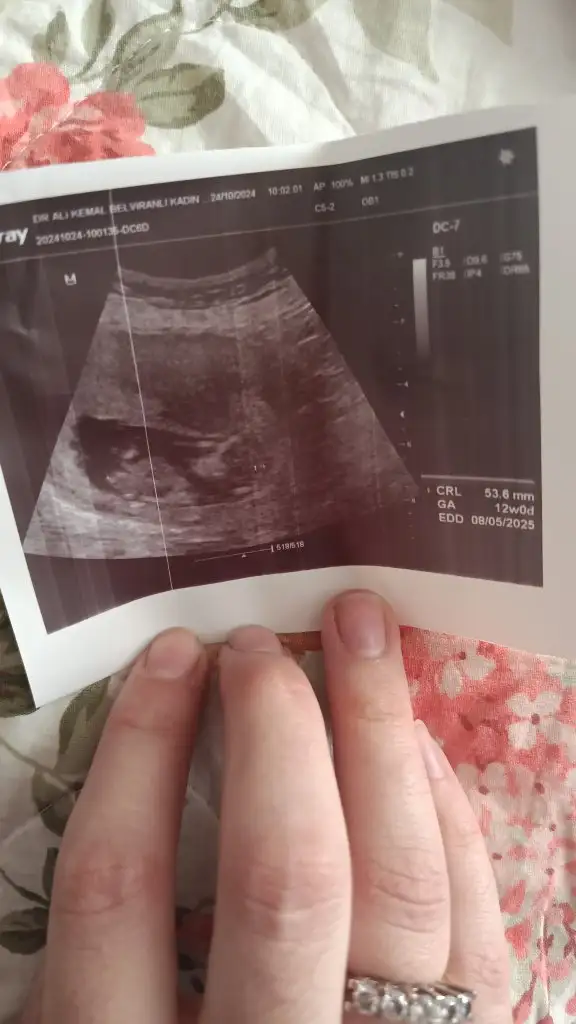

5 ve 14. haftaya kadar olan ultrason fotolarınızı paylaşın. Vajinadan mı yoksa karından mı çekildiğini ve kaç haftalık olduğunu da mutlaka belirtin.